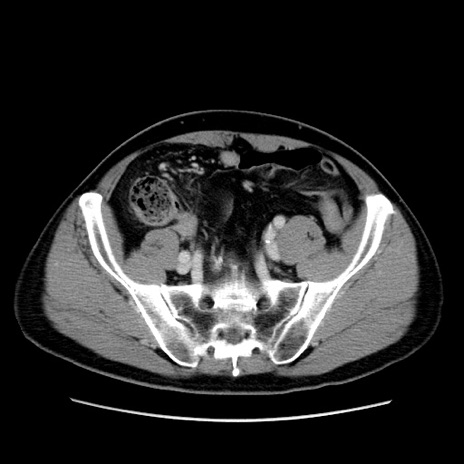

症例34(横断像)

【症例】60歳代 男性

【主訴】右鼠径部膨隆

【現病歴】1年程前より右鼠径部膨隆あり。自己にて還納可能だったため放置していた。3時間前より右鼠径部の脱出を認め、還納困難となり受診。

【既往歴】高血圧

【身体所見】右鼠径部に小児頭大の膨隆あり。弾性硬であり、用手還納は困難。左鼠径部にも膨隆を認める。脱出はなし。

【データ】WBC 15500、CRP 測定なし